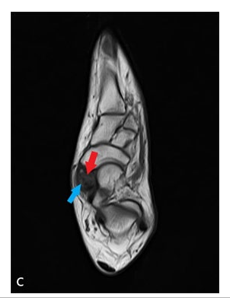

Axial T1W (c) and Sagittal T1W (d) MRI Shows that Hypointense Stress fracture line (blue arrow) and Hypointense Avascular Necrosis in the Type II ANB (red arrow).